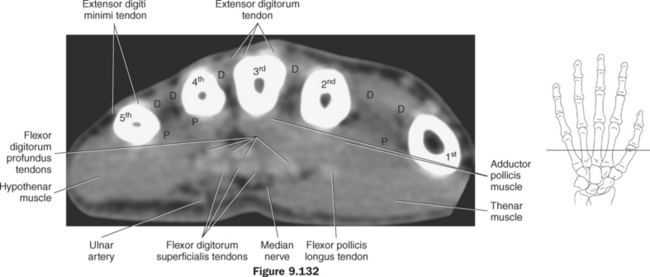

Figure 9.132 Axial CT scan through fingers.

Key: fl, Flexors; c, capitate; ex, extensor tendons; r, radius; l, lunate; D, dorsal interosseus muscles; P, palmar interosseus muscles.

The numerous muscles of the forearm become tendinous just before the wrist joint. The many tendons located in the wrist can be divided into palmar and dorsal tendon groups (Figures 9.120, A and B and 9.127). The palmar tendon group collectively flexes the fingers and wrist. As this group courses through the carpal tunnel, the tendons appear to be arranged in two discrete rows (Figures 9.118, A and 9.119). The tendons of the dorsal tendon group, spanning the superficial surface of the wrist, are considered the extensors of the fingers and wrist (Figures 9.128 through 9.140).

The muscles of the hand can be divided into three groups: (1) metacarpal group (muscles of the metacarpals considered to be the central muscles of the hand), (2) thenar group (muscles involving the thumb and creating the thenar eminence on the radial side), (3) hypothenar group (muscles involving the fifth digit and creating the hypothenar eminence on the ulnar side). These muscles are demonstrated in Figures 9.128 through 9.143.